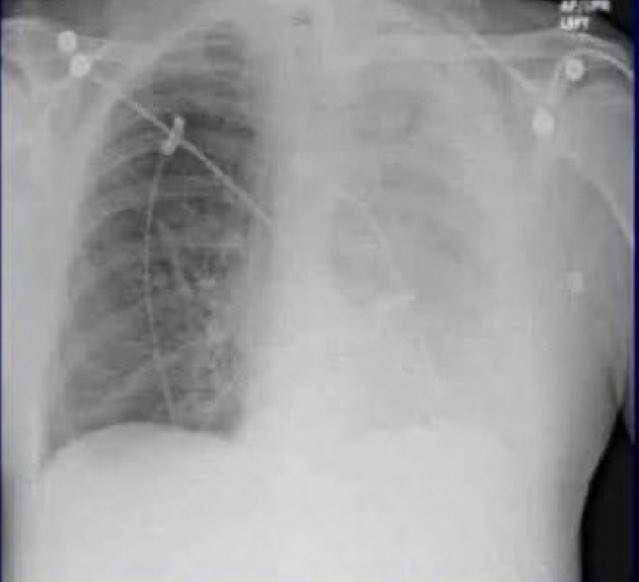

تم نقله إلى المستشفى ، وقام الأطباء بأخذ صورة بالأشعة السينية. ووجدوا أن إحدى رئتيه قد انهارت وشوهدت بقعة صغيرة على الأشعة السينية كان سفيدن متأكدًا الآن من أنه مصاب بالسرطان. لقد انتظر فقط حتى يتحدث الأطباء.

تبين أن اختبار السرطان كان سلبيا. وبدلاً من ذلك ، وجد الأطباء نبتة بازلاء تنمو من رئتيه. افترض الأطباء أن حبة البازلاء قد سقطت في الحفرة الخطأ في وقت ما

يبدو أن الظروف الدافئة والرطبة داخل الرئة جعلت منها مكانًا مثاليًا لنمو نبات البازلاء. بعد عملية جراحية بسيطة إلى حد ما ، تمت إزالة نبات البازلاء بطول 1.25 سم من رئته.